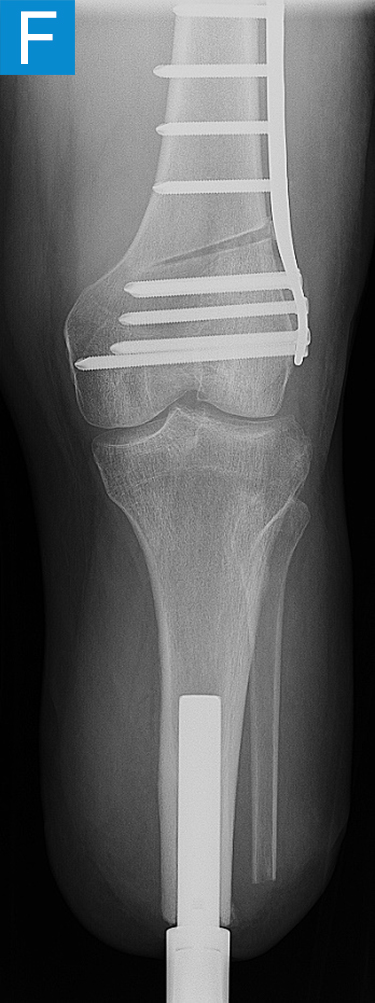

Figure 2. Postoperative clinical photos and radiographs. (A) Front and (B) rear views show the patient standing with the osseointegrated tibia prosthesis. (C) Photo shows stable and healthy skin at portal site to be, although slightly dry due to the winter weather. The gold-colored metal is part of the permanent transcutaneous implant; the shiny silver-colored metal beneath the gold is part of the clinician-removable prosthesis connector, and the matte silver metal beneath features a screw at the front, by which the patient secures the prosthesis. (D) Standing coronal radiograph depicts residual genu valgum in the osseointegrated leg. (E) Lateral radiograph of the osseointegrated tibia. (F) Coronal radiograph of the left knee shows the distal femur osteotomy. (G) Final coronal radiograph after distal femur plate and screw removal shows well-aligned left leg with osseointegrated prosthesis.